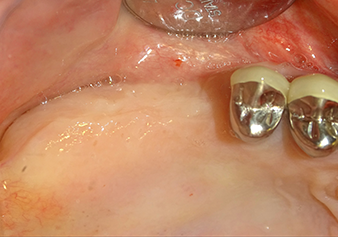

Implantation and prosthetic restoration

To move the augmentation material in the direction of the maxillary sinus atraumatically, the implant was inserted very slowly by hand (Fig. 9). In the process, the membrane was pushed in the cranial direction once again. After two months, the surgical site healed without irritation. Six months later, the x-ray check showed a significant increase in opacity as an indication of ossification (Fig. 10). The prosthetic restoration was carried out with a metal-ceramic crown.